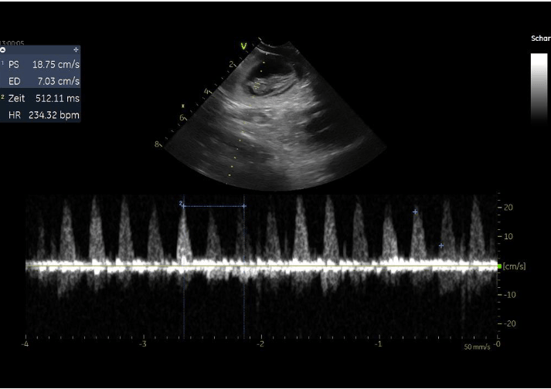

24.04.2020 - unser J Wurf ist unterwegs

Der Ultraschall am 21.04.2020 brachte Gewissheit. Unsere Daisy ist tragend. Wir freuen uns sehr auf unseren J-Wurf in rund 4 Wochen ❤️

05.02.2020 Unser I-Wurf ist unterwegs

Der Ultraschall brachte uns Gewissheit. Unsere Cassi ist tragend ❤ Beim Ultraschall wurden 6 Fruchtblasen gezählt. Wir freuen uns sehr und nun heißt es fleißig weiter brüten.  In rund 4 Wochen werden wir unseren I-Wurf begrüßen dürfen.